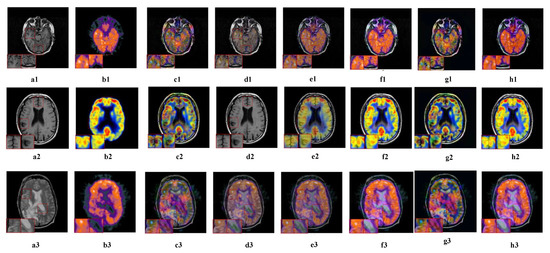

5.2.4. Fusion Analysis on MRI-PET

5.2.5. Fusion Analysis on MR-SPECT